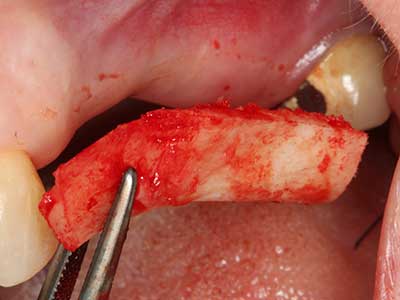

La piezochirurgia presenta altri vantaggi per quanto riguarda la raccolta di blocchi ossei. Oltre all'elevata precisione dell'osteotomia appena descritta, l'utilizzo di puntine per sega molto sottili permette di minimizzare in maniera significativa la perdita di materiale. È molto probabile che si verifichi una maggiore perdita di materiale durante la raccolta utilizzando puntine di strumenti più spessi, in particolare delle frese Lindemann (Lakshmiganthan, Gokulanathan et al. 2012). La separazione basale, necessaria in particolare per i trapianti di blocchi nella zona retromolare, viene semplificata grazie a seghe specificatamente progettate di forma rettangolare; di conseguenza la piezochirurgia è considerata una procedura precisa, semplice e sicura per la raccolta di blocchi di osso nella zona retromolare (Happe 2007) (figg. 1-12).